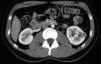

Urotomografía con datos de tumor renal izquierdo en tercio medio de 28×25mm cortical irregular, exofítico, de 30UH sin realce a la aplicación de medio de contraste, de aspecto quístico multiloculado con áreas solidas y septos discretos en su interior (Bosniak III) (fig. 1).

Figura 1.

Imagen de la lesión renal en un corte tomográfico en fase contrastada.